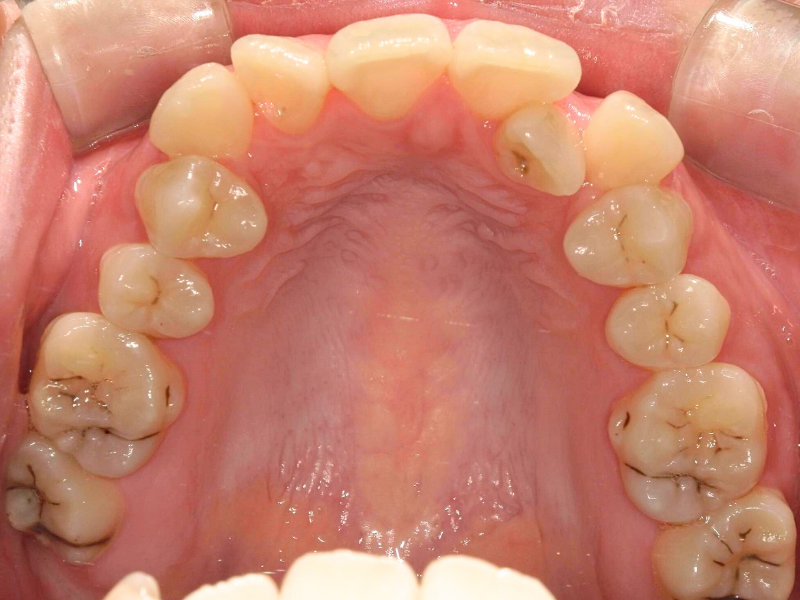

20代、女性、ワイヤー

| 施術内容 | 主訴:全体的に凸凹が気になる 詳細:ワイヤー矯正での歯並び改善 ずっと磨きにくく、臭いが気になっていましたが、 矯正後は磨きやすくなり、臭いも無くなって満足された症例です。 |

| 治療期間 | 16ヶ月(3/13現在 治療終了) |

| 費用 | ワイヤー矯正 60万円(税込660,000円) |